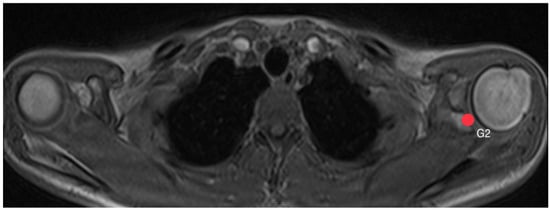

2.3. Acromion Index (Figure 1)